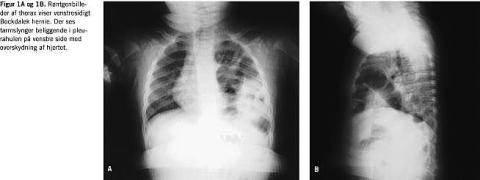

På børneafdelingen på Amtssygehuset i Glostrup har vi igennem de seneste to år diagnosticeret to tilfælde af sent debuterende medfødt diafragmahernier, patient nummer 4 i Tabel 1 (Figur 1A og 1B) samt patient nummer 3 i Tabel 2 (Figur 2A og 2B).

Fire pati enter med Bochdalek hernie havde potentielt alvorlige tilstande, idet to havde overskydning af hjertet, og to havde pulmonal hypoplasi, hvorimod patienter med Morgani hernie ikke havde alvorlige tilstande. Tre af de fire patienter med potentielt alvorlige tilstande var drenge, og tre havde venstresidigt hernie. Venstresidigt hernie fandtes hos 71% af patienter med Bochdaleck hernier og hos 43% af patienter med Morgagni hernier. Drenge udgjorde 86% af patienter med Bochdaleck hernier og 43% af patienterne med Morgagni hernier.

Man har tidligere haft den opfattelse, at sent medfødt diafragmahernie ikke er en livstruende tilstand, og at der kun findes minimale symptomer fra enten luftveje eller mave-tarm-kanal [7]. Vores undersøgelse kan ikke bekræfte dette. Ved debut havde to patienter overskydning af hjertet imod højre. Den ene patient havde periodisk cyanose. Begge patienter havde Bochdalek hernie. Der er beskrevet to tidligere raske børn, som pludseligt fik hjertestop og døde. Ved autopsi fandtes et Bochdalek hernie [7]). Desuden er der beskrevet død af en 14 mdr. gammel patient, der var kendt med gastro-øsofageal refluks. Barnet fik feber, opkastninger og blev respiratorisk og cirkulatorisk påvirket. En røntgenfotografering af thorax viste overskydning af hjertet imod højre pga. et venstresidigt diafragmahernie. Trods intensiv terapi fik barnet hjerte-stop og døde af hjerneanoxi. Det mediastinale skift imod højre kan obstruere det venøse tilbageløb til hjertet, og den gastrointestinal obstruktion øger dehydreringen, hvorved patient får hypovolæmisk shock med hjertestop til følge [7, 10].